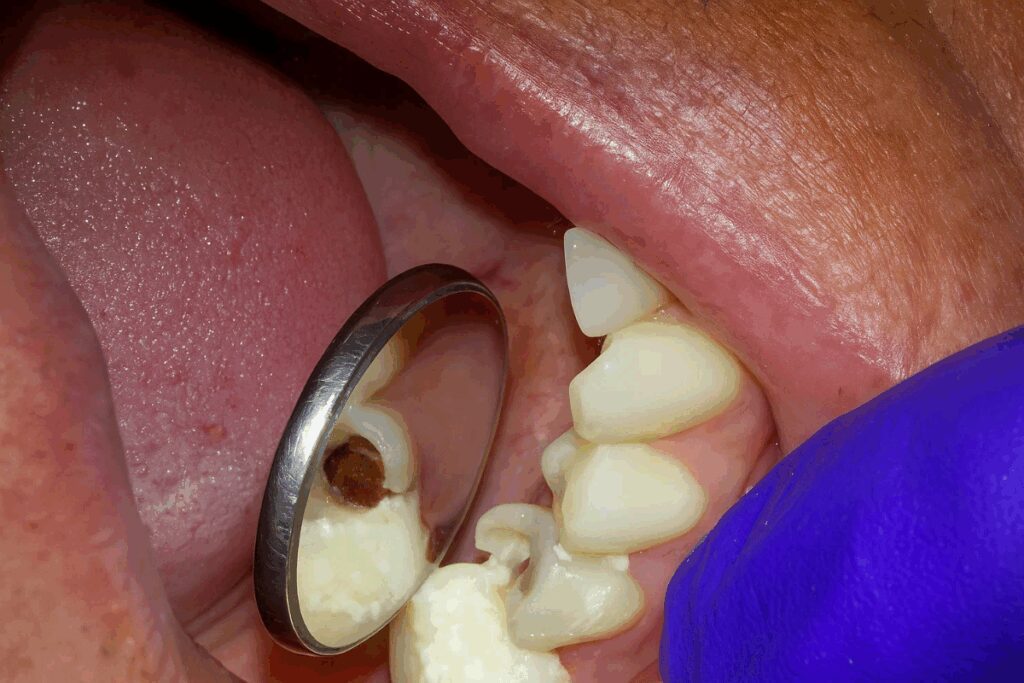

When the holidays arrive, dental issues that have been quietly simmering can suddenly require urgent attention. Cracked teeth from hard candies, abscesses triggered by infection, or aging fillings that finally give way under the pressure of Thanksgiving dinner are all common seasonal culprits.

Many dentists observe an increase in emergency visits around the holidays due to untreated issues and indulgent eating habits. Cracked teeth from nuts, candies, and holiday treats—as well as neglected issues that become urgent—are common reasons for emergency visits this time of year.

Root Canals: The Truth Behind This Tooth-Saving Treatment

Hearing the words “root canal” can cause anxiety—but modern root canal therapy is a safe, effective, and virtually painless way to eliminate infection, according to the American Association of Endodontists.

At Premier Dentistry, Dr. Patel uses advanced diagnostics and gentle techniques to remove infected pulp, clean the root canal, and seal the area to prevent future problems. Many patients report significant relief shortly after treatment, primarily when the infection is addressed early.